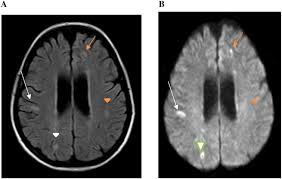

Guillain Barre Syndrome Mri / Figure 6 From Spinal Mri Findings Of Guillain Barre Syndrome Semantic Scholar - Typically, both sides of the body are involved, and the initial symptoms are changes in sensation or pain often in the back along with muscle weakness, beginning in the feet and hands, often spreading to the arms and upper body.. However, it can reveal nerve root enhancement and may be an effective diagnostic adjunct. Moreover, gbs is also associated with any vaccination. Its signs and symptoms are similar to those of other neurological disorders and may vary from person to person. Cerebral magnetic resonance imaging showed lesions in both frontal and right occipital lobes. Fisher syndrome, a clinical variant of guillain­ barre syndrome characterized by ataxia, are­ flexia, and ophthalmoplegia, brain stem lesions have been described with cranial mr.imaging (8).

Cerebral magnetic resonance imaging showed lesions in both frontal and right occipital lobes. Mri is sensitive, but nonspecific, for diagnosis. During a course of intravenous immunoglobulin therapy, she had headache with meningism. The most common result is a weakness and numbness that starts at the tips of the fingers and toes and spreads inward toward the body. Mr imaging findings in eight patients (three male, five female; 1 article features images from this case 14 public playlist includes this case Although no abnormalities were observed on brain and spinal magnetic resonance imaging and electroencephalography, peripheral nerve conduction velocity tests failed to evoke motor and sensory nerve action potentials. Typically, both sides of the body are involved, and the initial symptoms are changes in sensation or pain often in the back along with muscle weakness, beginning in the feet and hands, often spreading to the arms and upper body.